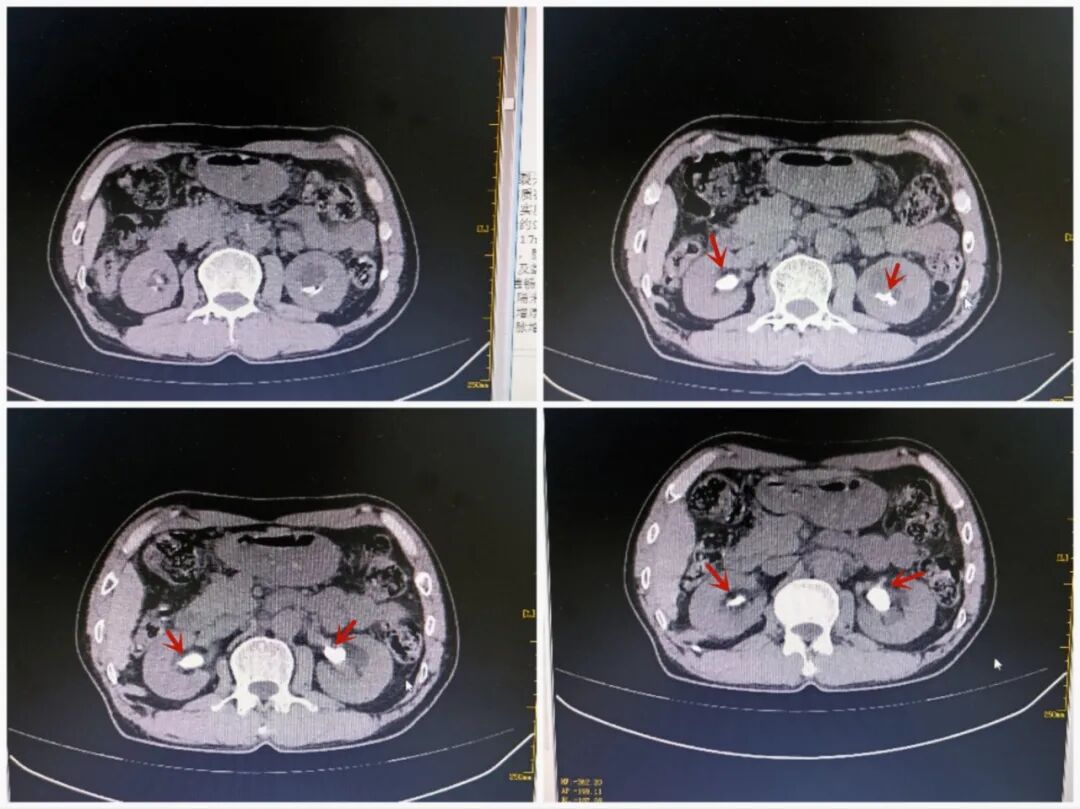

术前CT,唐大叔双肾巨大结石

患者唐大叔,反复受右侧腰部疼痛和血尿困扰,CT显示唐大叔双肾都有结石并伴有双肾积水,左肾结石最大直径3.5cm,接近一颗鹌鹑蛋大小!因唐大叔同时患有血小板减少症,辗转多家医院均被建议继续保守治疗或开展经皮肾镜取石。家属担心经皮肾镜取石手术的出血风险,迟迟不敢决定手术。